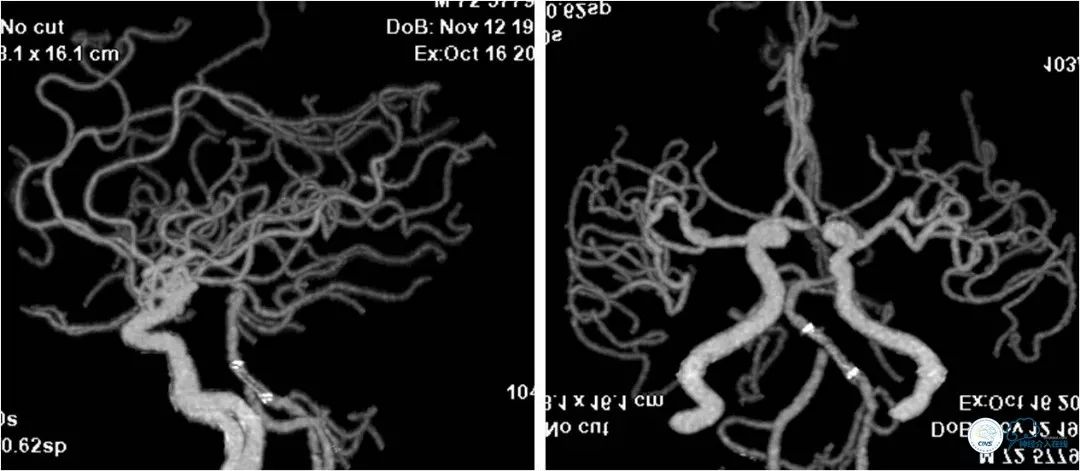

患者,男,72岁。主因“反复头晕3年”入院。患者3年前突发短暂头晕,无其他伴随症状,就诊于当地医院,行CTA提示:双椎动脉V4段-基底动脉交界区狭窄。3年来症状反复发作,多次行颅内动脉血管成像,显示病变程度逐渐加重(图1)。

图1